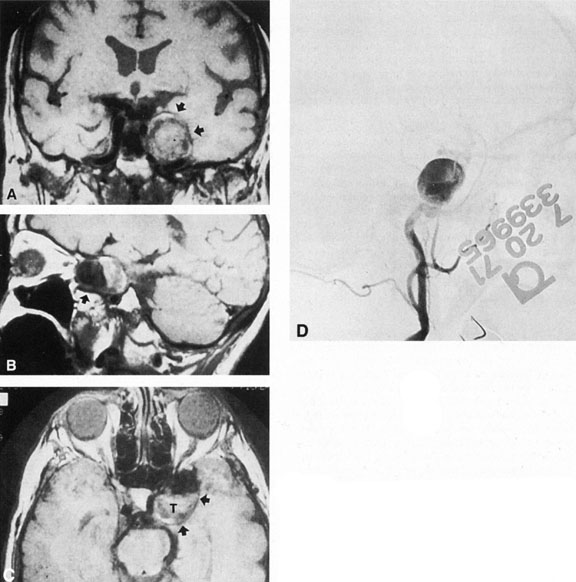

Fig. 3. Magnetic resonance images of intracavernous aneurysm in a 72-year-old woman with left retrobulbar pain and sixth-nerve palsy. A: Coronal section (TR, 800 ms; TE, 30 ms). B: Parasagittal section (TR, 1000 ms; TE, 20 ms). C: Axial section (TR, 800 ms; TE, 30 ms). Note partial occlusion by thrombus (T). D: In a similar patient, carotid arteriogram (subtracted, lateral view) demonstrates a large intracavernous aneurysm.

Intracavernous carotid aneurysms constitute only 2% to 3% of all intracranial aneurysms and are unique because of their location. These aneurysms arise from the internal carotid artery as it traverses the cavernous sinus4 (Fig. 3) and therefore produce a specific constellation of ocular and neurologic signs and symptoms. Rupture of such aneurysms, which are almost always saccular, may possibly result in carotid–cavernous sinus fistula, but subarachnoid hemorrhage is rare.5 However, slowly progressive enlargement is the rule, usually occurring within the cavernous sinus, with compression of the third, fourth, and sixth cranial nerves and later involving the first and second divisions of the fifth nerve (see Chapter 12).6 Progressive enlargement of the aneurysm forms a mass in the floor of the middle cranial fossa, compromising motor as well as sensory functions of the trigeminal nerve. Anterior expansion of the aneurysm erodes the anterior clinoid, optic foramen, and superior orbital fissure, eventually producing unilateral visual loss and exophthalmos. Posterior expansion, which occurs later, can erode the petrous portion of the temporal bone, causing ipsilateral facial palsy and, rarely, deafness. The sphenoidal sinus and the nasopharynx may infrequently be involved by inferior expansion and medial extension erodes into the sella and may simulate a pituitary tumor7 or cause bilateral ophthalmoplegia.8 Bilateral saccular intracavernous aneurysms occur uncommonly.9

Intracavernous aneurysms are suspected by the clinical presentation of a chronic cavernous sinus syndrome and are diagnosed by enhanced computed tomography (CT), magnetic resonance imaging (MRI), and arteriography (see Fig. 3). Because of the location and configuration within the cavernous sinus, direct surgical approaches to cavernous carotid aneurysms are hazardous. In recent years intravascular occlusion of the internal carotid by detachable balloon has evolved as a safe and successful procedure, often with relief of pain and improvement in ophthalmoplegia.10 Unfortunately, these balloons are commercially unavailable at the time of this writing.

Fig. 4. Giant suprasellar (supraclinoidal) aneurysms. A: Carotid arteriogram (lateral view) shows a huge aneurysm of the internal carotid artery in a 59-year-old woman with progressing visual loss. Coronal (B) and axial (C) magnetic resonance imaging sections of a similar case. Note partial thrombus formation (TR, 2100 ms; TE, 80 ms).

Most such aneurysms expand upward and forward, becoming located primarily anteriorly (Fig. 4). The optic nerves rise upward form the optic canal and may be inclined at a 45-degree angle such that the chiasm is more superiorly, as well as posteriorly, placed. It may be expected that uniocular ipsilateral visual loss would occur and progress before the contralateral field is involved because of chiasmal compression and before opposite nerve damage ensues. Although rapid visual loss has been reported, a longer duration (even years) is the rule. Rarely, the aneurysm may be more posteriorly placed or the chiasm more anteriorly fixed, resulting in initial involvement of the optic tract.20